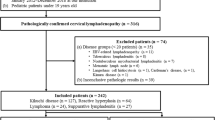

Among pediatric patients with lymphadenopathy who underwent lymph node excisional biopsy at Buddhachinaraj from January 2012 to December 2022, there were a total of 188 cases. These cases were categorized into three groups: reactive hyperplasia (91, 48.4%), benign lymphadenopathy other than reactive hyperplasia (70, 37.2%), and malignant lymphadenopathy (27, 14.4%) (Fig. 1).